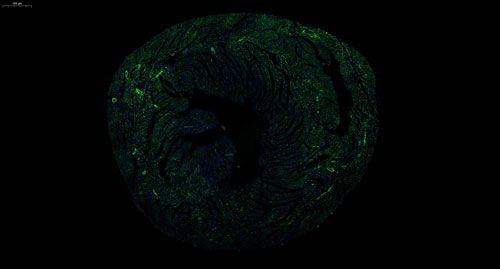

实验结果展示:

小鼠心 普通切片扫描(荧光单标 双色)